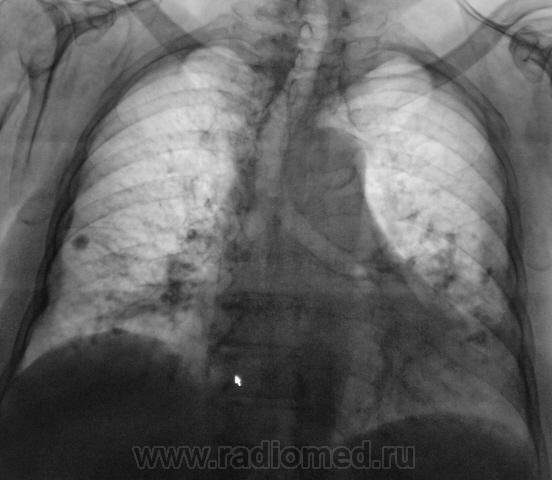

Пациентка взята на контроль после флюорографии.

Известно, что в течение 8 лет профилактической флюорографии не проходила. Обратиться в ЛПУ заставило кровохарканье. Пациентка - 92 года, практически жалоб не предъявляет.

Диффузно-очаговый базальный пневмофиброз с обеих сторон. Справа - крупный петрификат. Д\д-ка с гамартомой, периферическим раком, туберкуломой. Учитывая высокую плотность, сколняюсь к петрификату. Вообще, в этом возрасте при подобных фиброзных изменениях в легких (и, кстати, атеросклерозе) кровохаркание наблюдается нередко на фоне даже банального кашля. Было у меня несколько случаев "с ног до головы" обследованных пациентов (в т.ч. с ФБС) - кроме атрофии слизистой ТБД, цилиндрических бронхоэктазов и ломкости сосудов - ничего.